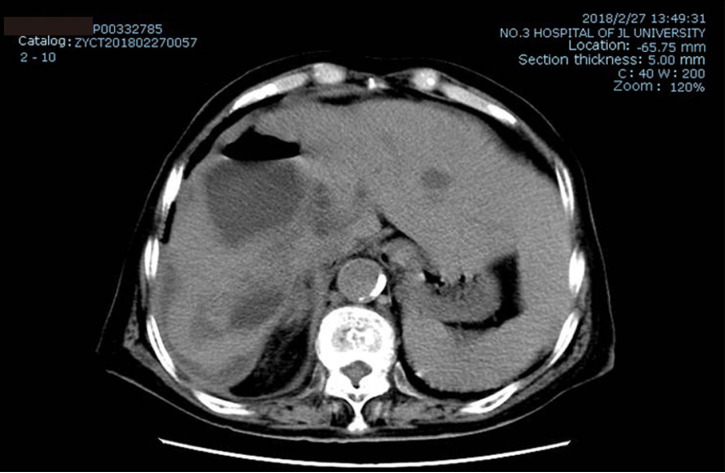

Imaging examinations

Following an initial abdominal ultrasound examination, an enhanced computed tomography (CT) scan was performed, which revealed multiple round cysts in the liver with clear boundaries. The largest cyst was located in the right lobe of the liver, with mild dilatation of the intrahepatic bile duct, and a size of approximately 20.1 cm × 12.2 cm × 19.6 cm. There was no contrast enhancement in either the arterial or venous phase (Figure 1).

Figure 1.

Enhanced abdominal computed tomography before treatment. A: Arterial phase; B: Venous phase; C: Balanced phase.